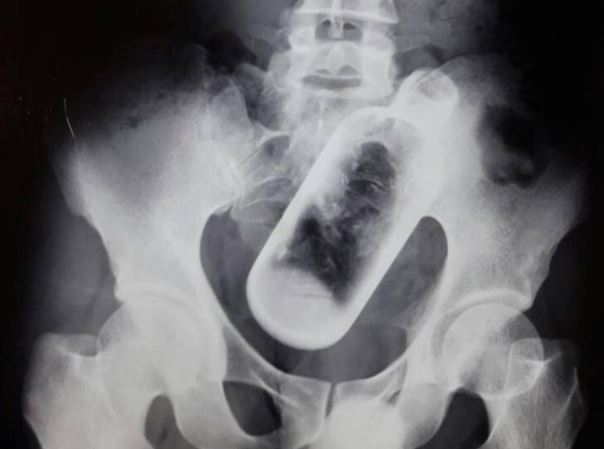

وأصيب الرجل بالصدمة عندما أدرك أن داخل معدته زجاجة طولها 16 سم، حيث فوجئ الأطباء بالزجاجة داخل جسمه بعد إجراء فحص بالأشعة السينية.

يذكر أن إزالة الزجاجة استغرقت 4 جراحين ونصف ساعة فقط في معهد مهراجا أجراسن للبحوث الطبية والتعليمية في الهند.